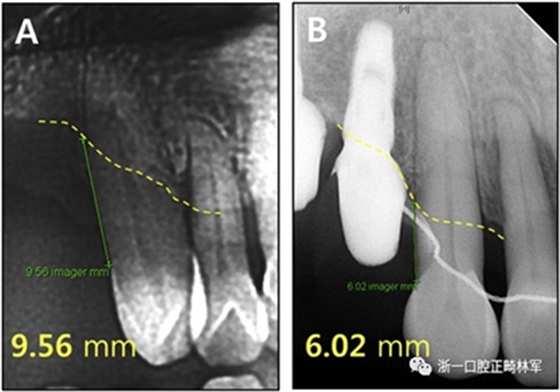

根據(jù)治療前后的根尖X光片,可以發(fā)現(xiàn)存在3.5mm顯著改善的放射線骨水平(圖15),并且臨床上牙周袋深度減少(表IV)。此外,力的推入性成分在向遠(yuǎn)中移動期間誘導(dǎo)了上頜切牙的推入,并且在根尖X線照片上看到牙槽骨水平的改善。

圖15.上頜右側(cè)尖牙放射性骨水平:A,治療前;B,治療后